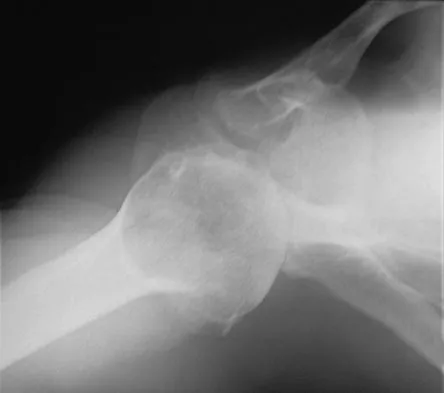

A 62-year-old man with a long history of right shoulder pain and weakness is scheduled to undergo hemiarthroplasty. Based on the radiographs shown in Figures 6a through 6c, what preoperative factor will most affect postoperative functional outcome?

Explanation

The radiographs reveal osteoarthritis and proximal humeral head migration. Integrity of the rotator cuff must be questioned based on these radiographic changes. The status of the rotator cuff is the most influential factor affecting postoperative function in shoulder hemiarthroplasty. The coracoacromial ligament provides a barrier to humeral head proximal migration in the face of a rotator cuff tear. The radiographs do not indicate significant humeral head or glenoid erosion. Acromioclavicular arthritis is often asymptomatic. Iannotti JP, Norris TR: Influence of preoperative factors on outcome of shoulder arthroplasty for glenohumeral osteoarthritis. J Bone Joint Surg Am 2003;85:251-258.